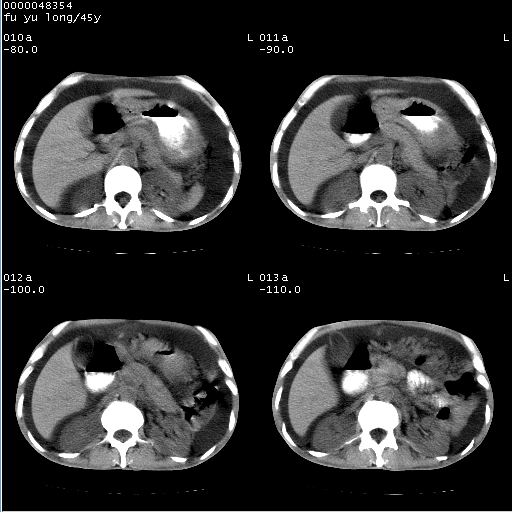

以下是引用lkc8963在2008-5-30 8:44:00的发言:[br]胃窦癌伴网膜(胃结肠韧带)/腹膜及腹膜后淋巴结转移.

以下是引用医影拾贝在2008-5-30 2:38:00的发言:[br]气肿性胃炎、胃十二指肠溃疡、腹膜炎,考虑穿孔可能性较大